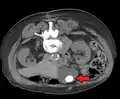

A 1.9 cm gallstone impacted in the neck of the gallbladder and leading to cholecystitis as seen on ultrasound. There is 4 mm gall bladder wall thickening.

Biliary sludge and gallstones. There is borderline thickening of the gallbladder wall.